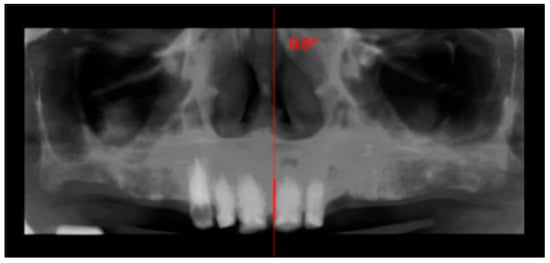

Figure 2.

Panoramic reconstruction derived from the CBCT volume showing the initial situation.